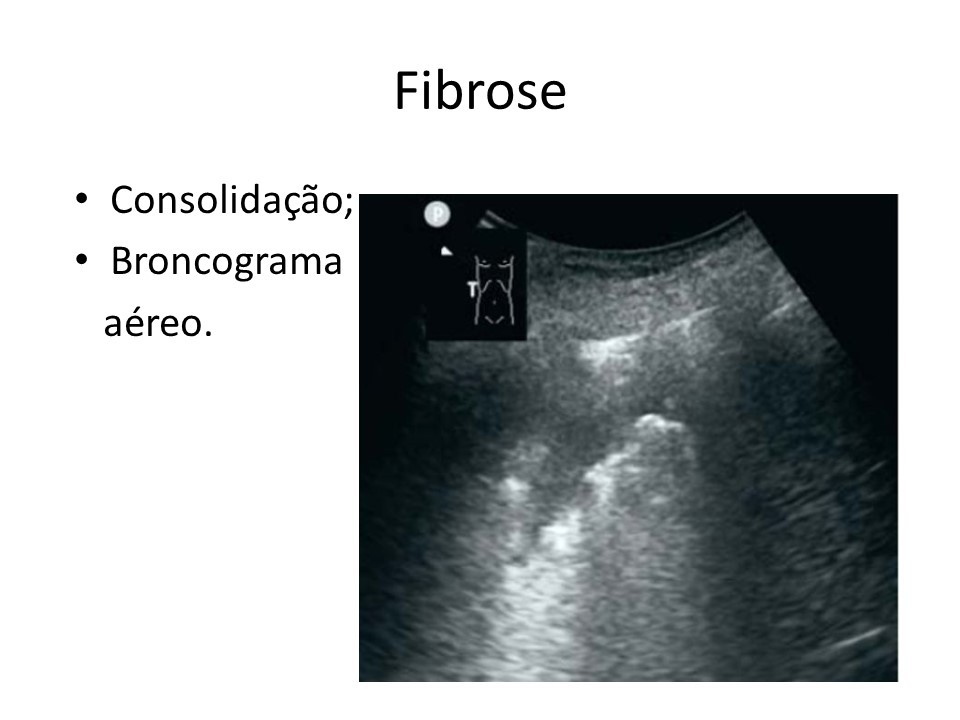

Você está aqui: Inicio Media imagem_dentro Imagem de ultrassom mostra marcas em pulmão com fibrose causada pelo coronavírus (Divulgação)

Imagem de ultrassom mostra marcas em pulmão com fibrose causada pelo coronavírus (Divulgação)